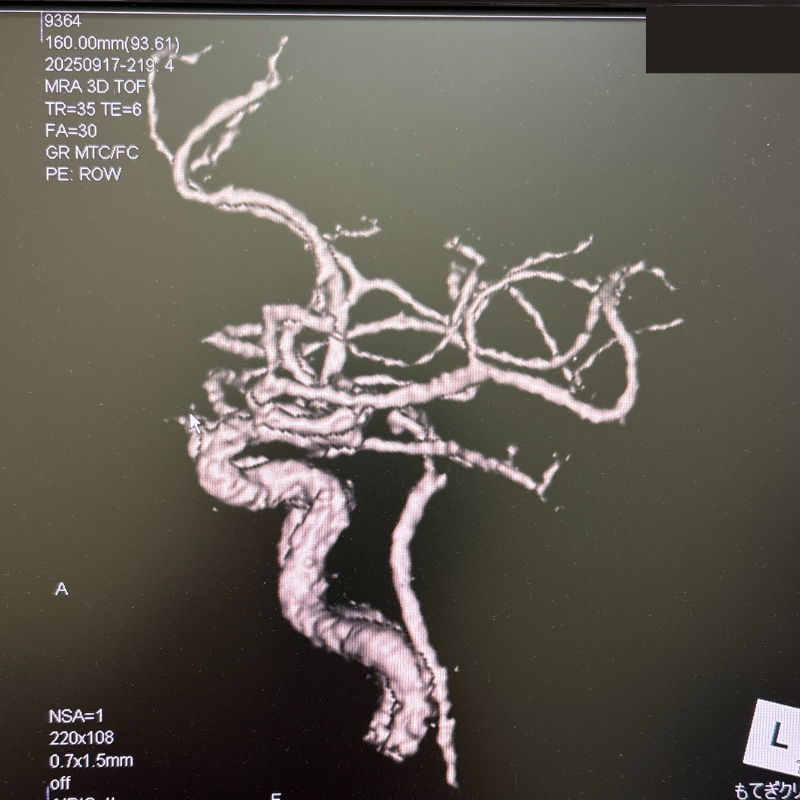

MRI画像例

下の画像は、当院で行うMRI・MRA検査で撮影できる脳の写真の一例です。

MRIでは脳の形や組織の状態を、MRAでは脳の血管の様子を詳しく確認できます。

当院では、CTやMRIで撮影した2D画像(平面画像)を3D画像(立体画像)に変換して表示できます。

立体的に確認することで、血管の通り道や狭くなっている部分、脳動脈瘤などの形をより詳しく観察することができます。

3D画像